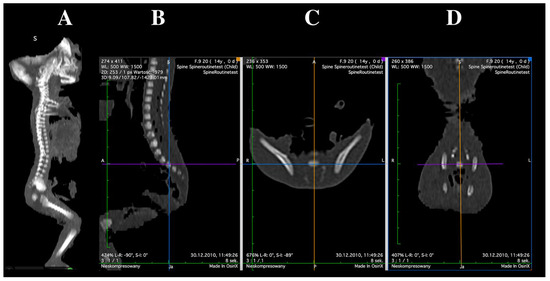

Three-Dimensional, Image-Based Evaluation of the L5 Vertebral Body and Its Ossification Center in Human Fetuses

by Magdalena Grzonkowska, Michał Kułakowski, Karol Elster, Zofia Dzięcioł-Anikiej, Beata Zwierko, Sara Kierońska-Siwak, Magdalena Konieczna-Brazis, Michał Banasiak, Stanisław Orkisz and Mariusz Baumgart

Brain Sci. 2025, 15(11), 1229; https://doi.org/10.3390/brainsci15111229 - 15 Nov 2025

Viewed by 713

Abstract

Objectives: The aim of this study was to characterize the developmental trajectories of the fifth lumbar vertebra in human fetuses by assessing the growth of its vertebral body and ossification center using linear, planar, and volumetric measurements. Methods: A total of 54 [...] Read more.

Objectives: The aim of this study was to characterize the developmental trajectories of the fifth lumbar vertebra in human fetuses by assessing the growth of its vertebral body and ossification center using linear, planar, and volumetric measurements. Methods: A total of 54 human fetuses (26 male and 28 female) aged 17–30 weeks of gestation were examined. Computed tomography, digital image analysis, 3D reconstruction, and statistical modeling were used to quantify morphometric parameters of the L5 vertebral body and its ossification center. Results: All measured parameters demonstrated consistent age-related growth following a linear pattern. No statistically significant differences between sexes were observed in any measured diameter of the L5 vertebra or its ossification center within the examined gestational age range. Conclusions: The normative morphometric data and growth curves obtained for the L5 vertebra and its ossification center provide age-specific reference values that may aid in prenatal diagnostics. These findings can support clinicians in estimating gestational age, assessing vertebral development on ultrasound, and detecting congenital spinal anomalies and skeletal dysplasias at an early stage. Further multicenter studies including a broader gestational age range are warranted to strengthen the generalizability and clinical applicability of these results. Full article

Show Figures